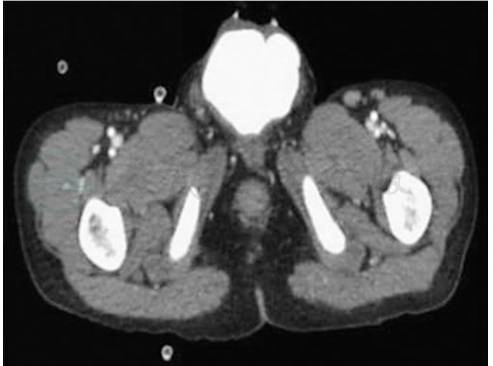

鉴于尿道结石大部分为草酸钙结石,因而传统X线检查可发现大部分结石。由于传统KUB平片往往无法观察到前尿道位置,建议对怀疑尿道结石的患者行盆腔正位X线检查(图1)。对于憩室或尿道狭窄合并尿道结石患者,逆行尿道造影不仅可以发现结石,更可提示尿道腔内及尿道周围组织的病变情况。超声可以明显发现前尿道结石,其声像图表现为尿道腔内强回声团块伴声影,当结石较小时可见结石随液体流动而滚动(图2)。后尿道结石,尤其是前列腺部结石往往在超声影像中误诊为前列腺钙化。这可能与前列腺钙化过于靠近尿道、患者肥胖、超声仪器分辨率低、检查者经验不足等因素有关。如条件许可,建议对怀疑后尿道结石患者行盆腔CT检查,在CT影像学多表现为尿道内高密度影(图3)。但仍注意需与前列腺钙化进行鉴别。盆腔MRI检查同样可发现结石,但MRI检查更大程度上有助于显示结石周围尿道管腔及尿道周围组织的病变情况。因其费用较高,操作时间较长,故而不作为尿道结石诊断的首选方法。

图3盆腔CT平扫尿道结石影像